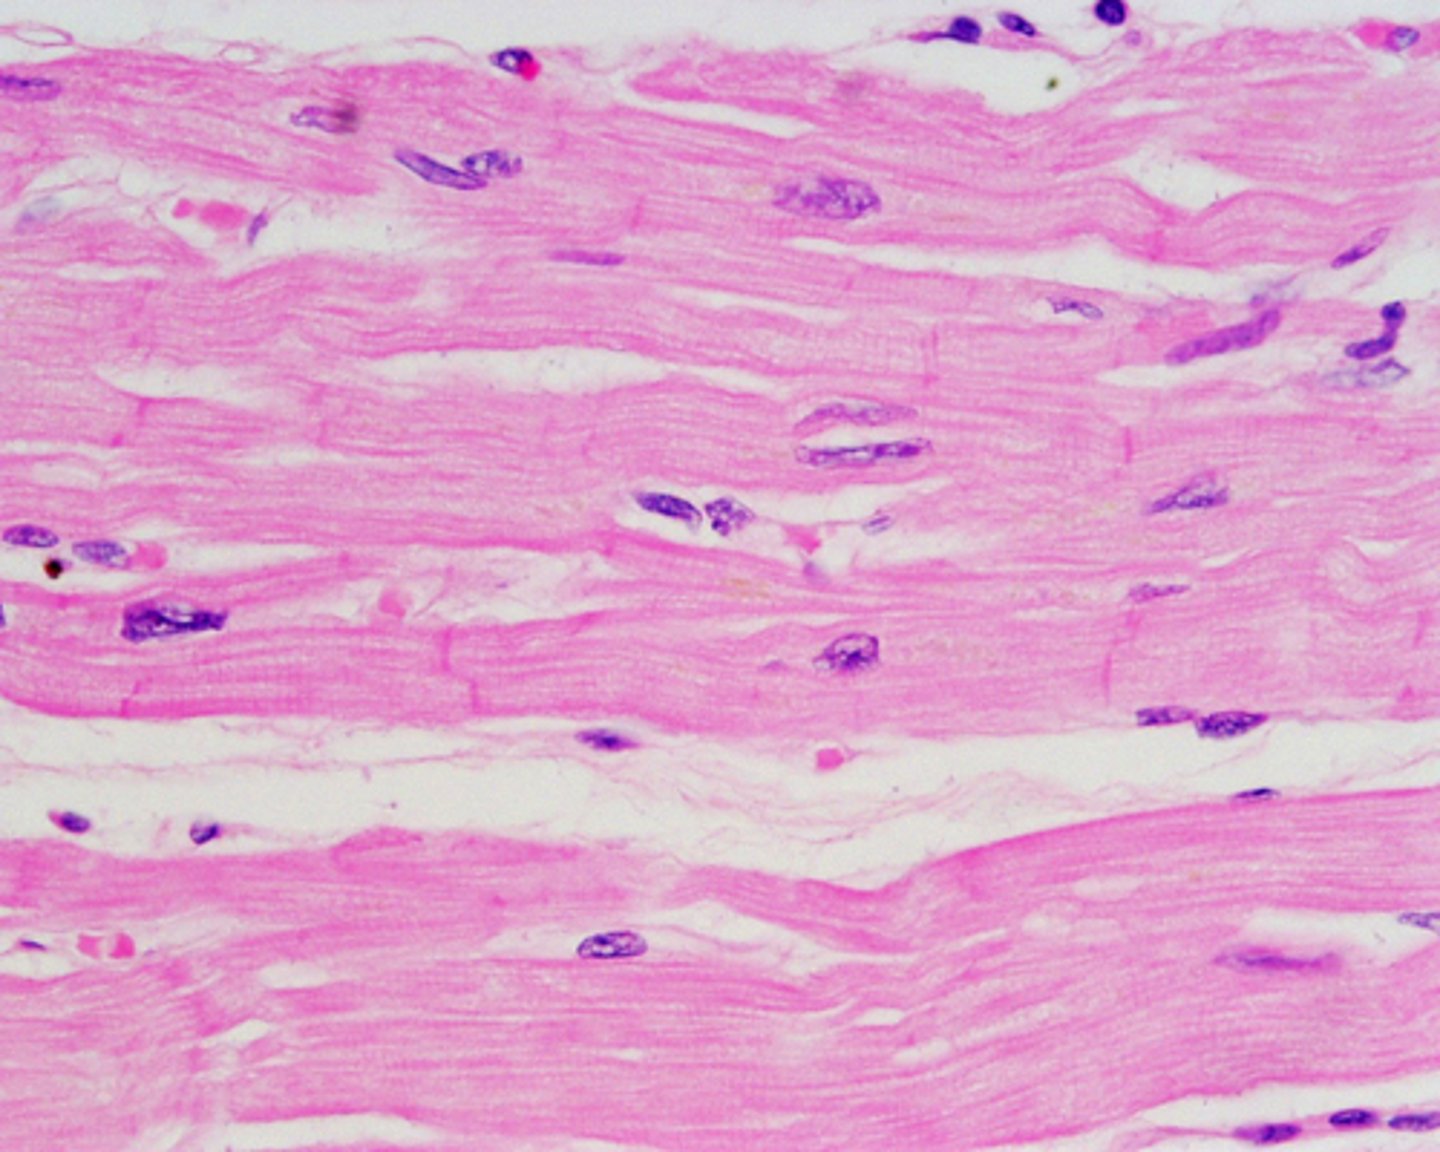

cardiac muscle

Involuntary muscle tissue is found only in the heart. comprised of heart and blood vessels.